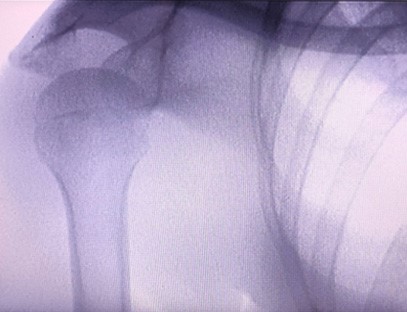

Prijenosni rendgenski aparatje vrlo siguran prijenosni instrument s niskom dozom zračenja koji može dobiti visokokvalitetne slike uz smanjenje izloženosti zračenju. Kompenzira nedostatke velike bolničke opreme i može se pomicati i nositi u bilo koje vrijeme. Posebno prikladno za jedinice i pojedince s nedovoljnim proračunom i malim zahtjevima za slike. Naš rendgenski uređaj nove generacije opremljen je velikim zaslonom visoke razlučivosti od 10 inča, koji ima veći raspon kuta gledanja i može u potpunosti vidjeti kroz cijeli dlan, uključujući prijelome, iščašenja, artritis i tumore kostiju. Može se spojiti na filmski pisač za ispis ortopedskih filmova, a može se koristiti i za industrijsku proizvodnju i testiranje. Nema potrebe za mračnom komorom, izravna perspektiva, promatranje u stvarnom vremenu. Ovaj stroj ima slikovni sustav visoke rezolucije koji može vrlo jasno uhvatiti slike bilo koje koštane strukture. Osigurati najbolju opremu i rješenja za testiranje rendgenskih zraka za proizvođače medicinskih, kućnih ljubimaca, industrijskih i elektroničkih proizvoda, odjele za inspekciju i održavanje te istraživačke laboratorije.

Specijalizacija:Dizajniran za potrebe ortopedskih klinika, posebno pogodan zaRentgensko snimanjeudova kao što su ruke, zglobovi, laktovi, ramena, koljena, gležnjevi itd.

Jasna slika:Napredna digitalna tehnologija snimanja koristi se za dobivanje visokokvalitetnih rendgenskih slika, pomažući liječnicima da točno dijagnosticiraju stanje.